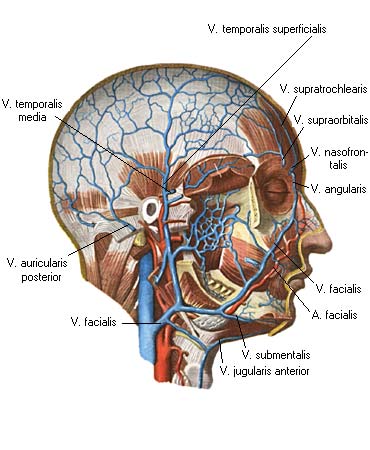

Анатомия внутренней яремной вены: КТ изображения